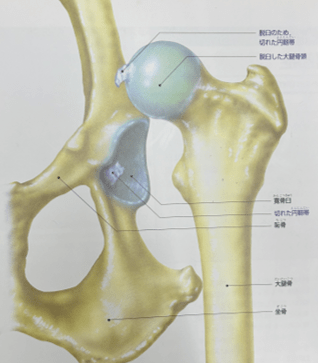

股関節は、骨盤のくぼみ(寛骨臼:かんこつきゅう)に、太ももの骨の先端(大腿骨頭:だいたいこっとう)がボールのようにはまり込む形をしています。この関節は強靭な円靭帯、関節包、筋肉で支えられており、犬がスムーズに歩いたり走ったりするために非常に重要な役割を担っています。

股関節脱臼とは、この「ボール」の部分である大腿骨頭が、「受け皿」である寛骨臼から完全に外れてしまった状態を指します。関節が外れることで強い痛みが生じ、正常に体重を支えることができなくなります。小型犬から大型犬まで、どんな犬種でも起こる可能性がありますが、特にトイ・プードルなどの小型犬で多く見られます。

参照「イラストでみる犬の病気|講談社」